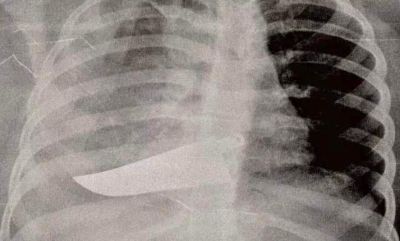

“Ecco l'orrore quotidiano che vediamo al pronto soccorso. Le donne, spesso, non hanno la forza di raccontare. Ma i corpi e le lesioni parlano per loro, rivelano vertigini di orrore quotidiano. Per questo abbiamo deciso di mostrare la violenza domestica come la vediamo noi al pronto soccorso: ossa rotte, nasi spaccati, occhi pesti, mani fratturate, polsi slogati, gambe rotte, coltellate, bruciature, morsi, segni di strangolamento, ferite da torture con pezzi di vetro. O addirittura un pugnale nella schiena (come nella foto). Lo scenario di una guerra nascosta”...

“Ecco l'orrore quotidiano che vediamo al pronto soccorso. Le donne, spesso, non hanno la forza di raccontare. Ma i corpi e le lesioni parlano per loro, rivelano vertigini di orrore quotidiano. Per questo abbiamo deciso di mostrare la violenza domestica come la vediamo noi al pronto soccorso: ossa rotte, nasi spaccati, occhi pesti, mani fratturate, polsi slogati, gambe rotte, coltellate, bruciature, morsi, segni di strangolamento, ferite da torture con pezzi di vetro. O addirittura un pugnale nella schiena (come nella foto). Lo scenario di una guerra nascosta”...

Il 21 novembre 2019, sono state messe in mostra, all'ospedale San Carlo di Milano, le radiografie delle vittime della violenza degli uomini sulle donne: uno spettacolo sconvolgente.

Curatrice dell’esposizione la chirurga Maria Grazia Vantadori con la Fondazione Pangea.